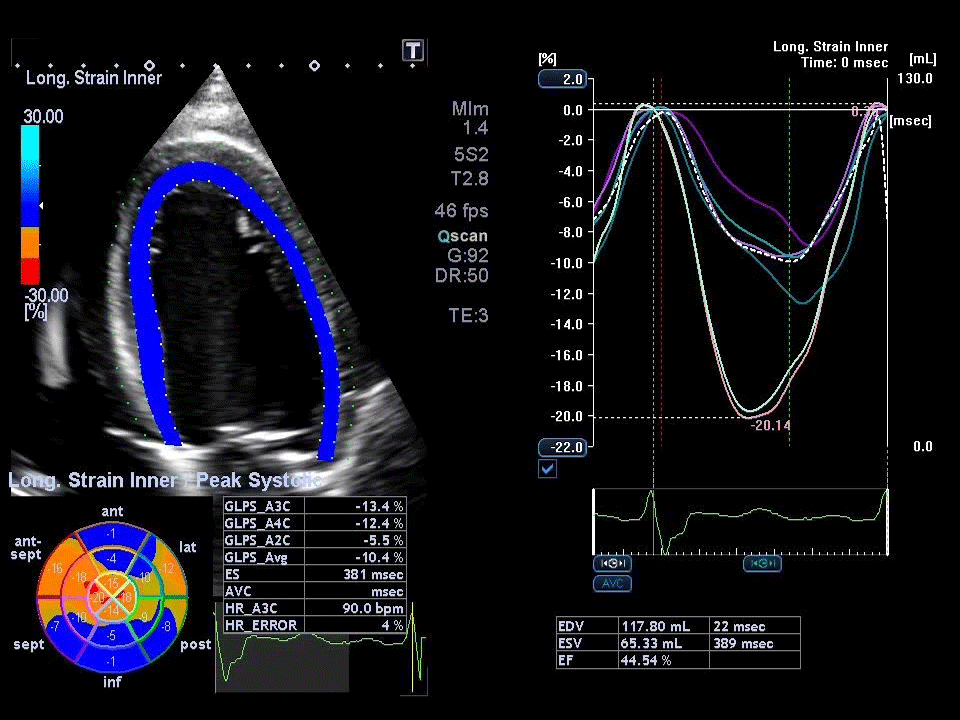

Ecocardiograma com Strain

O Ecocardiograma Strain é uma tecnologia avançada do ecocardiograma que permite analisar de forma detalhada a função do músculo cardíaco, identificando alterações sutis na contratilidade do coração antes mesmo de surgirem sintomas ou disfunções visíveis nos exames tradicionais. Esse exame é fundamental para detectar precocemente problemas como cardiomiopatias, efeitos de quimioterapia sobre o coração e outros danos que podem comprometer a função cardíaca.

Na NovaCardio, o Ecocardiograma Strain é realizado com equipamentos de última geração e interpretado por especialistas, garantindo um diagnóstico preciso e um acompanhamento personalizado.